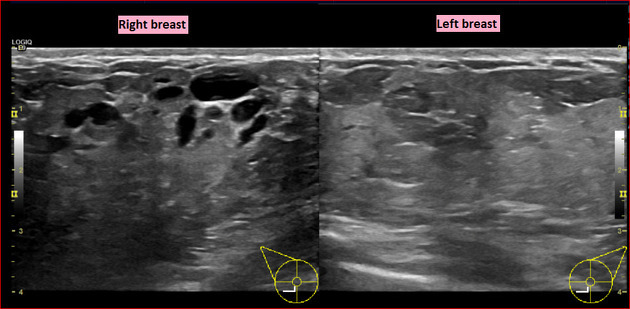

The affected side (left side here) show diffuse, relatively ill-defined, echogenic breast fat tissue and increased colour flow Doppler, and enlarged lymph nodes in the axilla, with no evidence of focal skin thickening or traction, well-defined mass, or nearby extra-breast tissue invasion.

The dilated lactiferous ducts are of similar appearance bilaterally, without evidence of wall thickening or internal echogenic component or debris.

Comparison of the normally appearing, non-affected (right side here) breast and axilla demonstrate the difference in echogenicity, architecture, axillary lymph nodes, (shown), and vascularity (right side not shown).